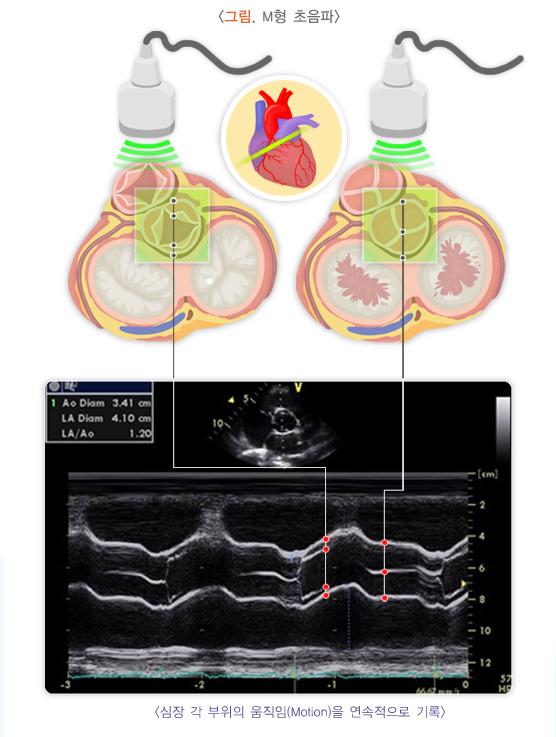

하대동맥혈관염은 초기 증상이 미미하거나 비특이적인 경우가 많기 때문에 조기 진단이 어렵습니다. 주로 초음파, CT, MRI 등의 이미징 검사와 혈액 검사를 통해 염증 상태와 대동맥의 변화를 평가합니다. 정기적인 추적 검사가 중요하며, 치료와 경과를 모니터링하기 위해 지속적인 검사가 필요합니다.